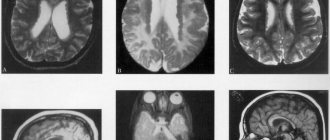

The early childhood (infantile) form - Tay-Sachs disease - begins at the age of 4-6 months. Often the disease is familial. Decreased vision is detected early. The child cannot fix his gaze and does not follow the toys. Quite early, the “cherry pit” symptom is detected in the fundus - a cherry-red spot in the macular area, surrounded by a grayish-white rim.

Subsequently, optic nerve atrophy and complete blindness develop. Indicative and defensive reactions disappear. Movement disorders lead to complete immobility. With Tay-Sachs disease, a symptom of an increased reaction to sound stimulation is observed - children flinch sharply from a normal sound, and convulsions may be observed, which are predominantly tonic in nature. In the final stage of the disease, cachexia and a state of decerebrate rigidity develop. Death occurs on average 11/2-2 years after the onset of the disease.

The late childhood form of Bielschowsky-Jansky begins at 3-4 years. The course is progressive, with remissions. Increasing organic dementia is combined with general convulsive seizures, ataxia, and extrapyramidal disorders. Atrophy of the optic nerves is detected in the fundus. Some authors deny the nosological independence of the late childhood form of Bielschowsky-Jansky and consider cases of this disease as a manifestation of the early onset juvenile form of Batten-Spielmeyer-Vogt or as later variants of Tay-Sachs disease. Death in most cases occurs at the end of the first decade of life.

The juvenile form of Batten-Spielmeyer-Vogt begins at the age of 6-10 years and is characterized by a slowly progressive course. The fundus picture often corresponds to retinitis pigmentosa. The disease begins with a gradual decline in vision and increasing dementia. Changes in the motor system can be different and inconsistent: mildly expressed tetraparesis, extrapyramidal and bulbar disorders are observed. Epileptiform syndrome is not uncommon. The disease ends in death in the 2nd—3rd decade of life.

Late amaurotic idiocy of Kufs is extremely rare, occurs in adulthood and is characterized by a sluggish course. Personality changes develop according to the type of organic mental syndrome. The fundus reveals a picture of retinitis pigmentosa with atrophy of the optic nerves. In the late stage of the disease, paralysis and epileptiform syndrome develop. Patients usually die within 10-15 years from the onset of the disease.